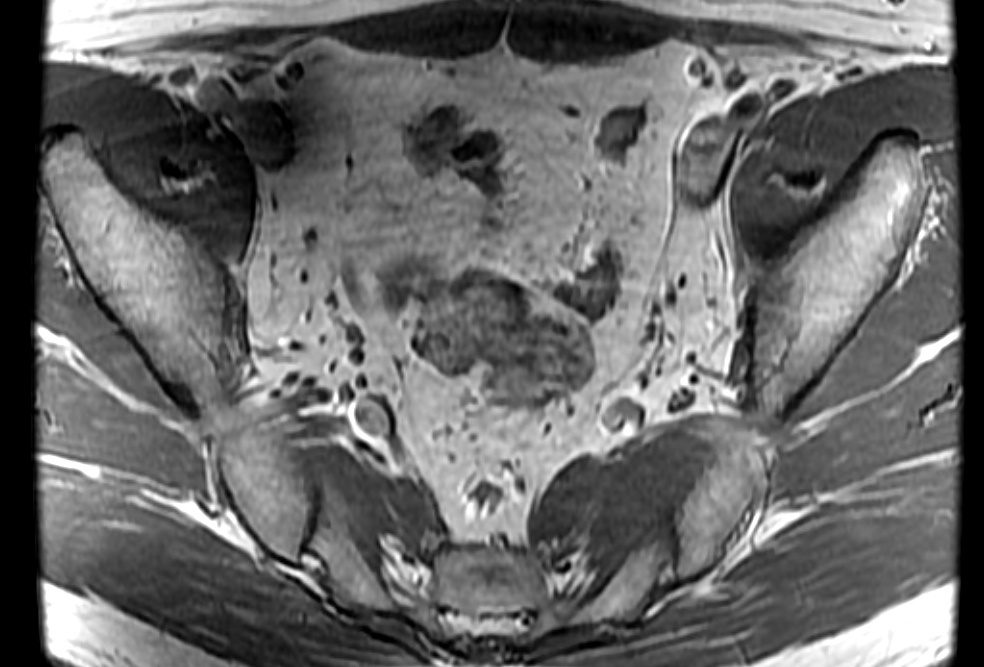

Bilateral accessory piriformis muscles at the S2 level attaching to the sacral body, anterior the S2 nerve roots. Normal piriformis muscles should be posterior to the sacral nerve roots. The result is that the S2 nerve roots may be pinched between the piriformis and accessory piriformis muscles.

Bilateral accessory piriformis muscles